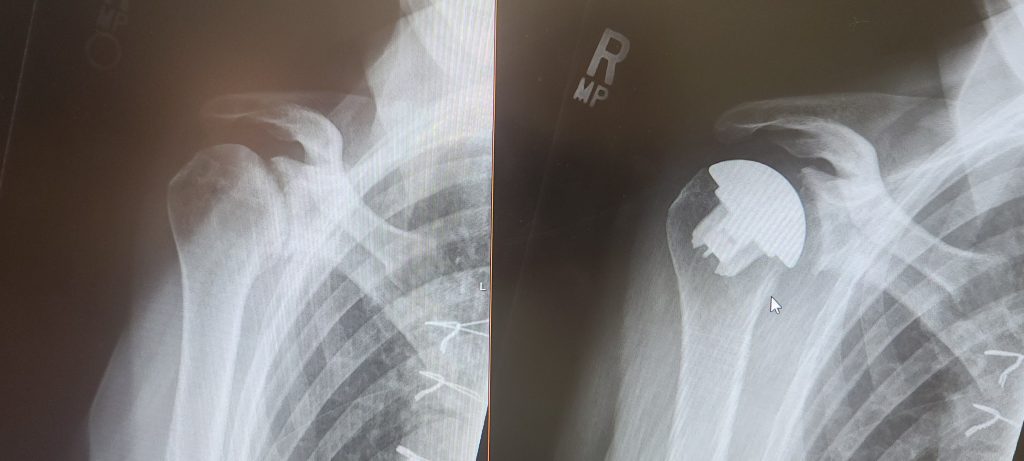

Dr. Jesse Charnoff has been my non-surgical doctor several years now. He has helped me a great deal. Through his expert knowledge and devoted care he helped me with injections to relieve the pain I felt with my shoulder. It came time where there was no recourse but to have surgery. Dr. Charnoff recommended Dr. Christopher Brusalis who replaced my arthritic bone-on-bone shoulder with a new improved replacement. It was nothing short of a miracle for me. I worked hard in physical therapy as he suggested and I can move my arm all around with no pain or discomfort. Truly an amazing surgery and surgeon. I am so happy to know both doctors. I trust their expertise. Thank you very much.